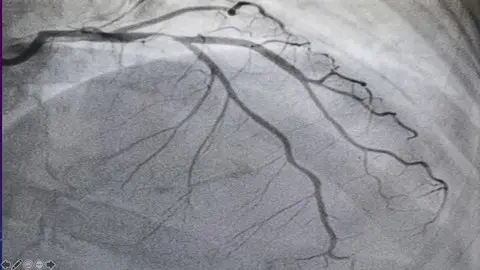

Coronary Angiography Certificate Course

coronary angiography

Angiography report interpretation

Lecture 2 Practical examples of angiography

Lecture 7 Target lesion in angiogram

Lecture 8 Coronary angiogram view summary